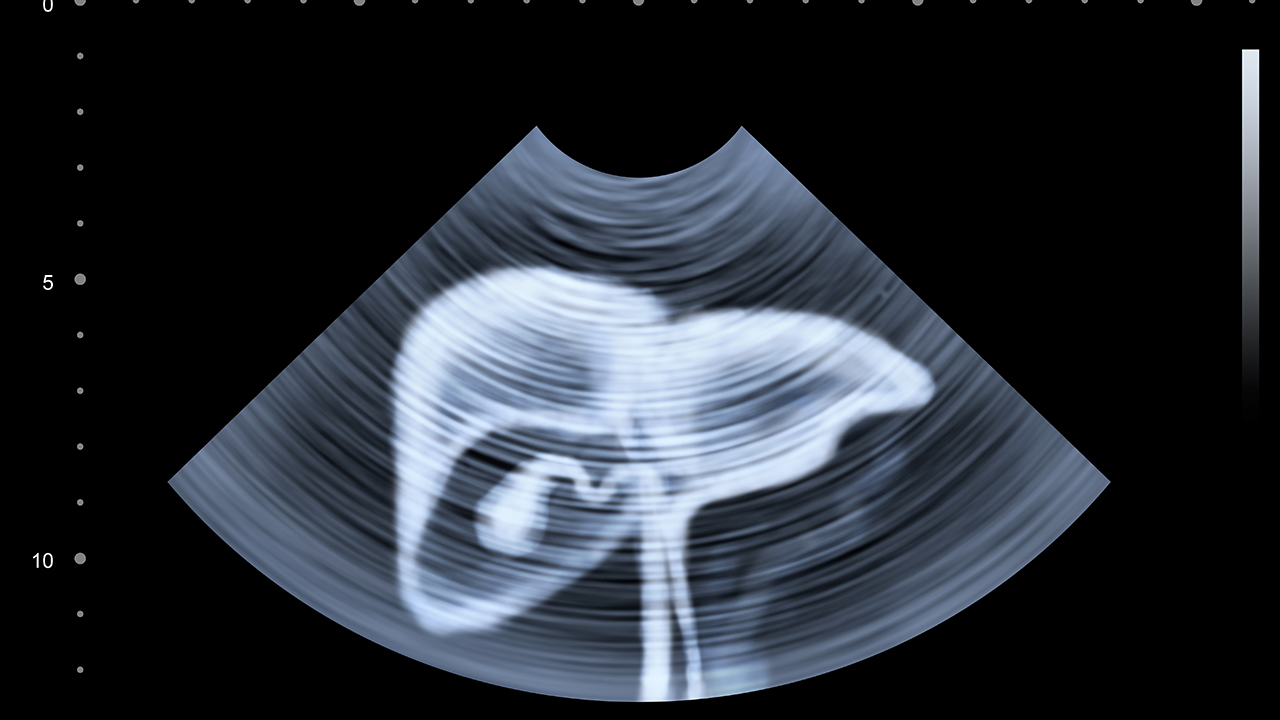

肝癌的预防与健康管理至关重要。对于高危人群,如慢性肝炎患者、肝硬化患者、长期酗酒者等,应定期进行肝脏检查,包括肝功能检测、甲胎蛋白检测和肝脏超声检查等。保持良好的生活习惯,避免酗酒,注意饮食卫生,避免食用霉变食物。接种乙肝疫苗是预防肝癌的重要措施。对于已经确诊的肝癌患者,应积极配合治疗,定期复查,保持良好的心态,合理饮食,适当运动,提高生活质量。